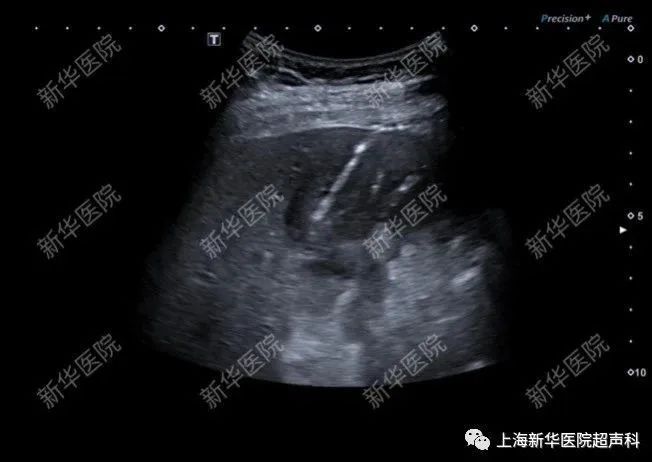

(3)超声引导粗针穿刺组织学活检:乳腺肿块(BI-RADS4类及以上或部分3类病变)、异常肿大淋巴结、浅表组织占位性病变、肝肿瘤、肝肾弥漫性病变等需明确病变良恶性或病理类型等,为确定治疗方案提供依据,可在超声引导下进行粗针穿刺活检,获得完美的组织学标本。

肝肿瘤穿刺活检术

(5)超声造影实时引导和超声造影-MRI/CT影像融合导航:超声造影实时引导有助于确保活检获得活性组织,避免穿刺坏死组织;超声造影与CT/MRI融合导航下实时引导,有助于定位及诊断肝内隐匿性微小病灶,扩大了穿刺及消融治疗的适用人群及范围。

肝肿瘤超声造影